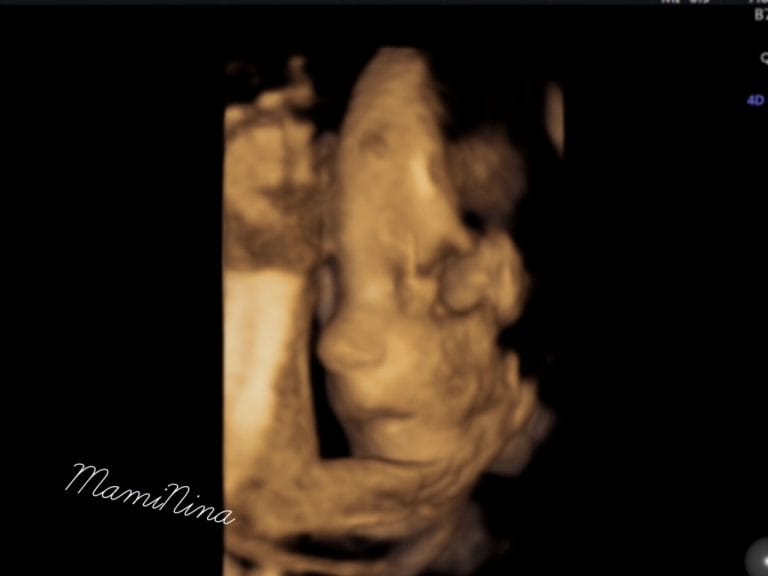

Teža: ostaja ista, glede na praznike pa najbrž ne bo več dolgo takšna Obseg: 93cm Punčka Ta teden meri nekaj malega preko četrtine metra in že tehta 1,2 kg. Velika je približno toliko kot tale ročna lutka. Tako močnih premikov kot so bili prejšnji teden tokrat ni bilo, res se zdi da so vedno bolj…